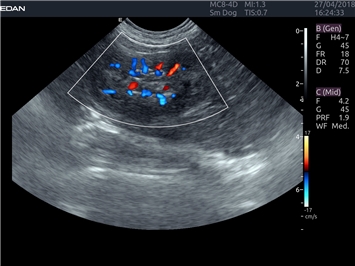

УЗИ-аппарат

EDAN Acclarix LX4 VET

EDAN Acclarix LX4 VET представляет собой профессиональную ультразвуковую систему, специально разработанную для ветеринарных исследований. Сочетание стабильности, высокой производительности и эффективности делает эту систему идеальным выбором для современной ветеринарной практики.

Цветовой допплер:

Да

Трехмерная реконструкция ЦДК: